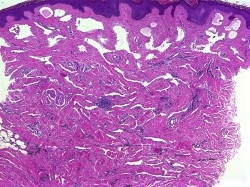

This biopsy was obtained from an annular pigmented plaque on the trunk, what is this neoplasm?

Targetoid hemosiderotic hemangioma

Targetoid Hemosiderotic Hemangioma: Occurs most commonly on young adult males on the trunk and named for its clinical appearance. The lesion typically appears as a plaque with concentric rings, there is violaceous central region surrounded by a ring of pallor which is then surrounded by an erythematous or brown rim. Histologically in the superficial dermis there are dilated blood vessels, some of which have plump hobnailed endothelial cells. In the deeper dermis the vessels have a narrower lumen and dissect between the collagen bundles. Often within the lesion there are extravasated red blood cells and hemosiderin.

Target Sign